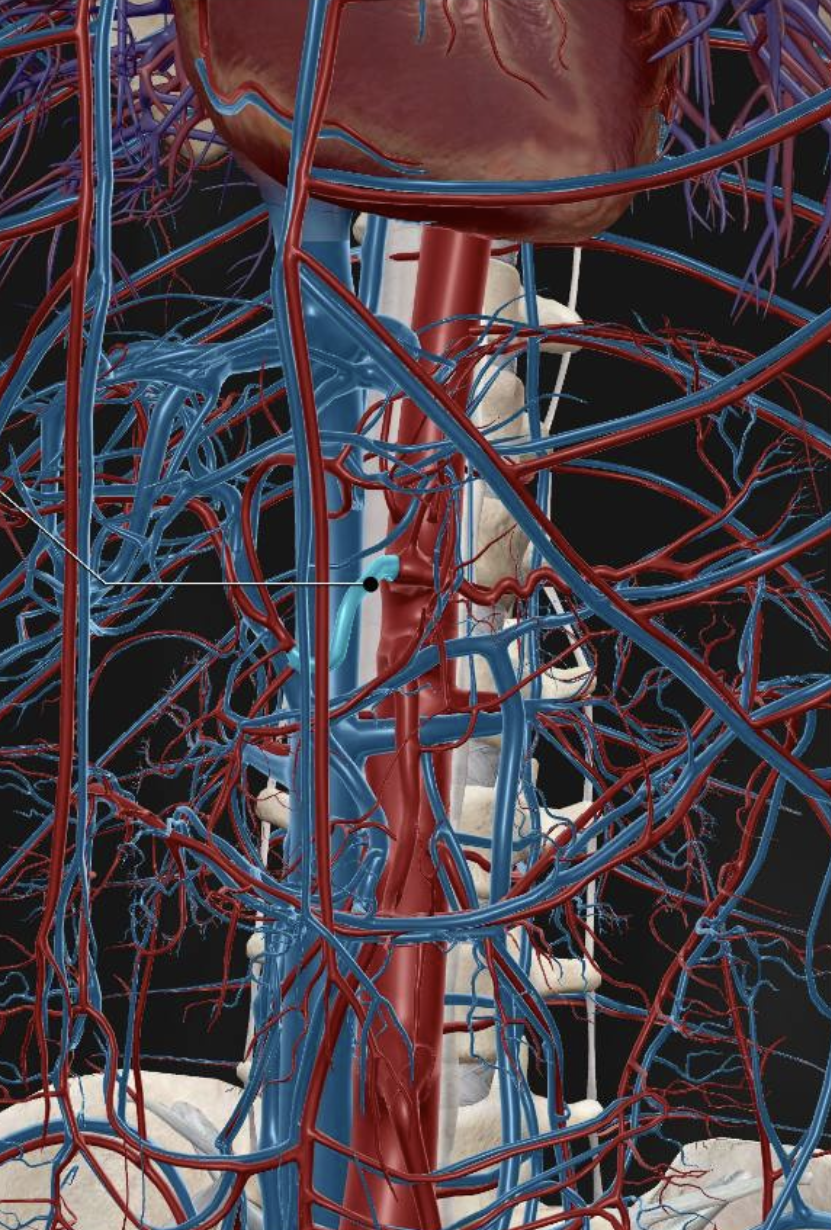

Inferior Vena Cava

Abdominal Aorta

Common Iliac Vein

Superior Mesenteric Vein

Inferior Mesenteric Vein

Renal Artery